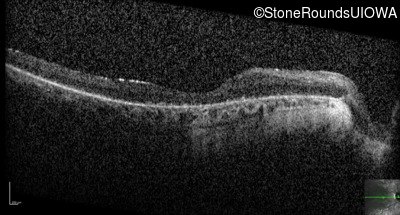

Optical Coherence Tomography - Left - 5/225

Exemplar / OCT Stack

OCT Stack